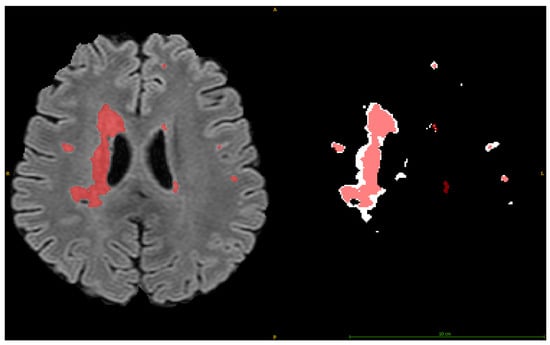

2.4.3. Volume, Positional, and Intensity Analysis

3.3. Single Component Position Evaluation

3.4. Single Component Intensity Evaluation